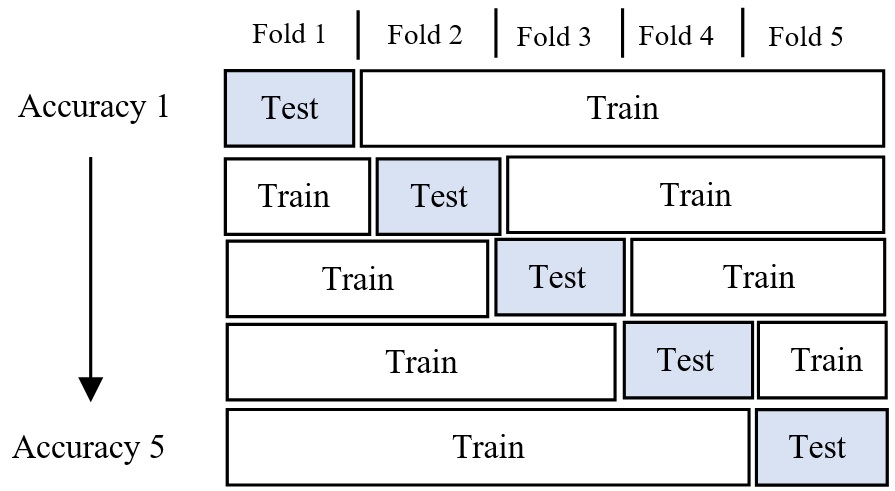

For this experiment, the bagging approach is adopted to maximize performance. Each network is trained using k-fold cross-validation. The mean accuracy is measured across each fold of the trained models as seen in Figure 4. The output classification of the three selected networks is then grouped into a majority vote classifier ensemble neural network. A majority vote classifier takes the mode of the binary classifications as seen in Figure 3 [28, 29].

MATLAB Programming Language was used to train the transferring learning models. VGG16, GoogleNet, ResNet18, and ResNet50 are all CNN Models, which were pretrained on a subset of the ImageNet dataset which was used in the ImageNet Large-Scale Visual Recognition Challenge (ILSVRC), which consists of thousands of class labels and over a million images. For each network, the last three layers – fully connected, SoftMax, and classification layer are replaced with the weights randomly initialized. Each network was trained for 15 epochs with a batch size and learning rate of 8 and 0.00005, respectively. Both, stochastic ‘gradient descent with momentum (SGDM), optimizer and adaptive moment estimation (Adam) optimizers are used in the training process. The learning rate that is used for models’ training is constant, shuffle is performed each epoch. As a cross-validation method, k-fold is chosen as a strategy to combat the limited data samples. The dataset split was 20% test set and 80% training set in each fold. The K-fold cross-validation is used to ensure that each observation from the raw dataset can appear in both the training and testing set. Results were obtained using 5 different k values (1-5). Then each network is combined into a bagging ensemble neural network. This bagging ensemble uses a majority vote classifier which takes the mode of each output of the combined neural networks as seen in Figure 3. It is expected that a bagging ensemble will outperform any individual network model.